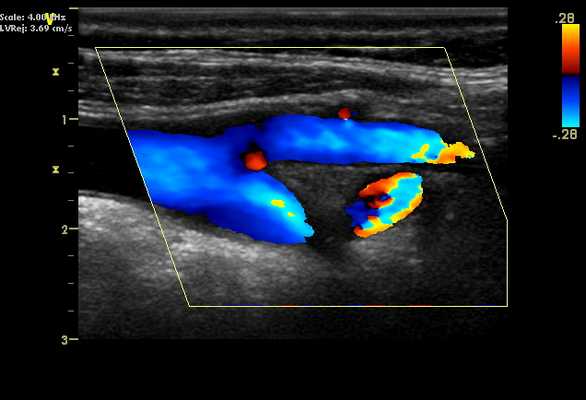

Наружная сонная артерия на УЗИ. Наружная сонная артерия обычно расположена перед внутренней сонной артерией. Обычно она меньше в диаметре по сравнению с ВСА и имеет несколько ответвлений в шейной области. НСА визуализируется путем направления звукового луча к лицу на уровне бифуркации.

Внутренняя сонная артерия на УЗИ. Внутренняя сонная артерия обычно расположена заднебоковой по отношению к наружной сонной артерии, но существует множество анатомических вариаций. Проксимальный сегмент ВСА (луковица) обычно больше в диаметре по сравнению с дистальными сегментами. Диаметр ВCA будет сужаться дистальном сегменте сосуда. В шейном отделе ВСА нет отходящих ветвей. Первая большая ветвь внутренней сонной артерии - глазная артерия. На УЗИ должны быть сделаны исследование проксимального, среднего и дистального сегмента внутренней сонной артерии.